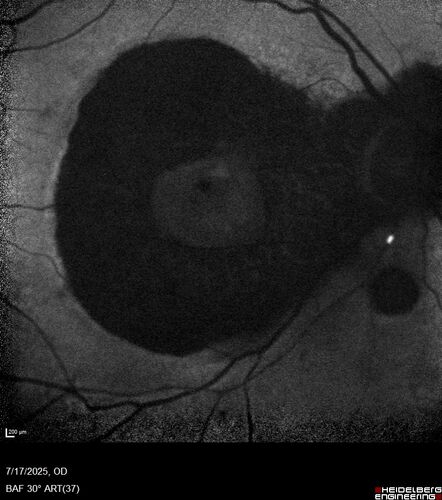

BRAO - plaques in vessels - GIF video of FA

78 year old female with vision loss for 1 week and old macular scar. Images show BRAO with plaques and FA shows occlusion.